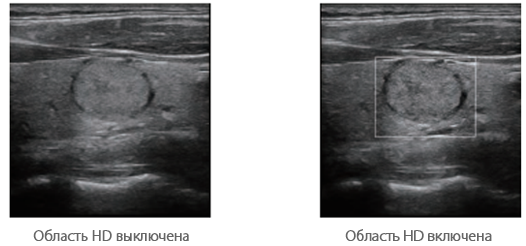

Область HD: более четкое изображение в пределах области интереса.